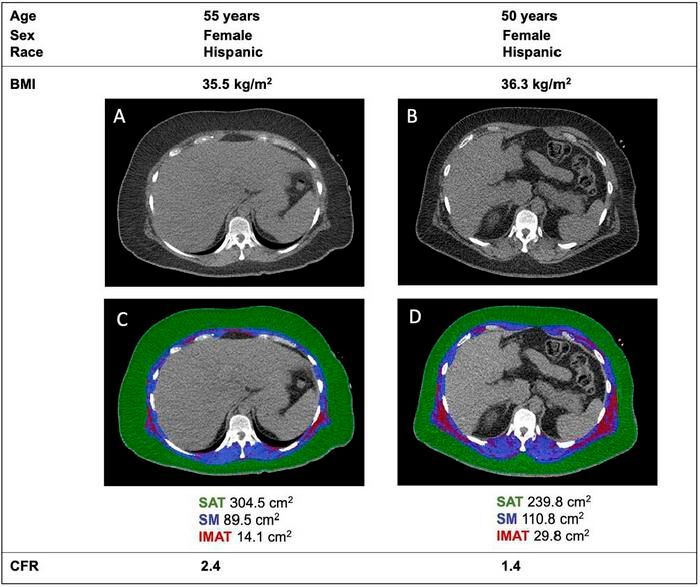

Hidden Fat in Muscles Linked to Higher Heart Disease Risk